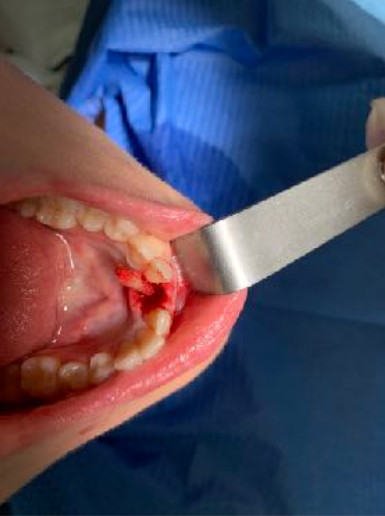

The reduced diameter of the neck allows you to protect yourself from any peri-implantitis and significantly improves the speed of healing. In this case it was tapped with a diameter of 4 and a Tramonte implant with a diameter of 4 mm with 7 threads with short neck was inserted. The titanium used is always grade 4.

| Type of implant : Tramonte | N ° implants inserted: 1 |

| Welding: No | Dental area: lower incisor 31 |

| Extractive situation: Immediate post-extraction implant with immediate loading. | Density according to Misch: D2 |